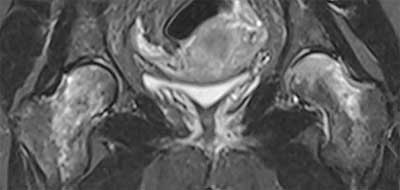

Figure 3

Bilateral osteonecrosis of the femoral heads postpartum: AP a) and lateral b) and c) Radiographs show flattening and condensation of both femoral heads.